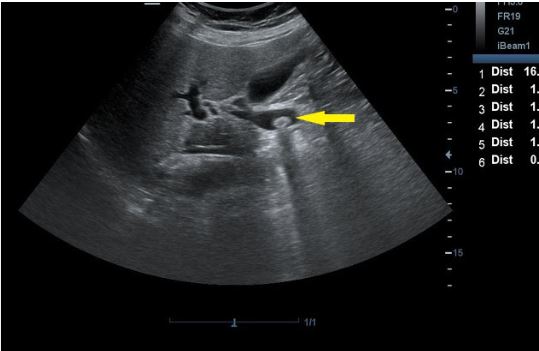

arrow is pointing to?

CBD

hartmann’s pouch

arrow: CBD

curved arrow: CBD

Common Bile Duct doesn’t catch COLOR

SAG - CBD

what are the arrows pointing to?

cystic duct

On this sagittal image, the hepatic artery (HA) is shown anterior to the common duct (CD)